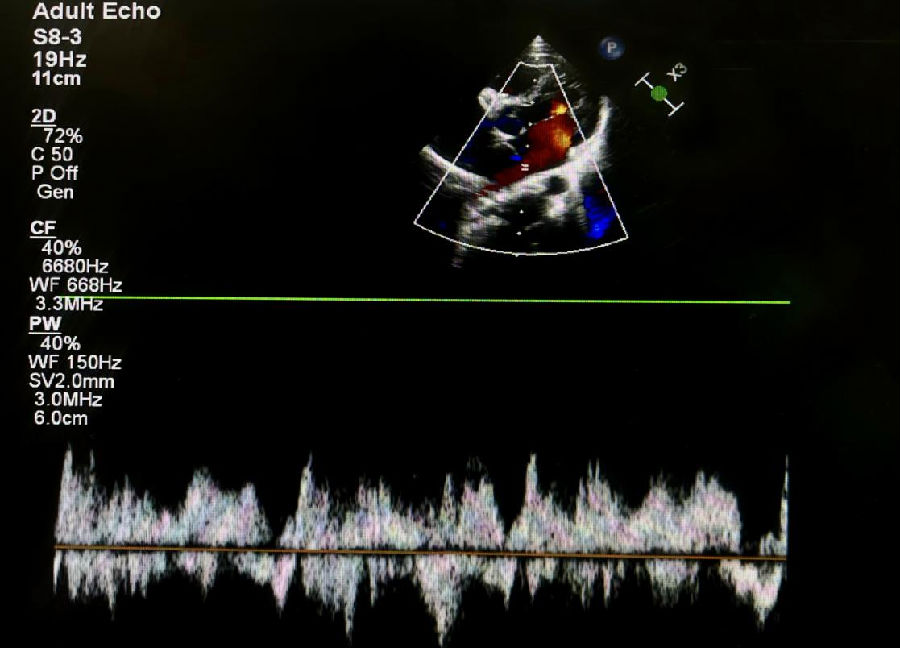

在体检中,有时可以通过听诊检测到心脏杂音。杂音的强度取决于血流通过隔膜的速度。超声心动图(经胸或经食道)是评估三房心解剖学和生理学的主要成像方式,彩色多普勒下的花色血流信号通常表示血流的加速和湍流的出现,这表明可以通过血流通过隔膜时可能有梗阻。经食管超声心动图的成像优于经胸超声心动图,可以明确的诊断三房心,并区分真正的左心房、左心房附属物以及隔膜的形态和梗阻程度。三维超声心动图是一种新的诊断工具,可以给临床提供额外的信息,能够明确隔膜的大小、位置和开口数量等。